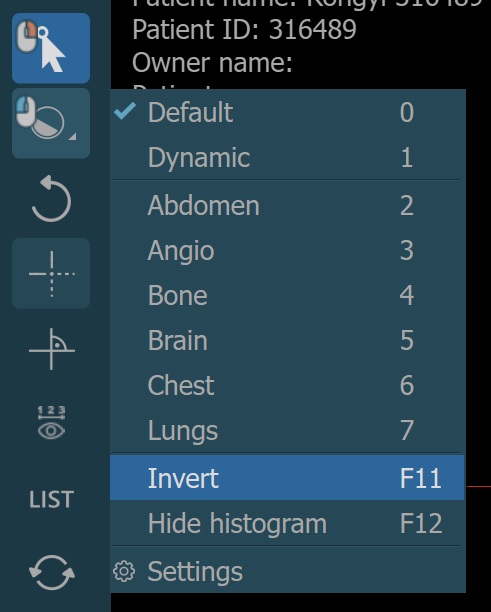

There are two different windowing modes available in the CT Viewer, Default and Dynamic. Change the active windowing mode by using the menu when selecting the Windowing tool.

Additionally, choose one of the available windowing presets from the dropdown to directly apply the corresponding window center and window width values.

The windowing presets are also available from the windowing menu when the default windowing mode is active.

Invert Image¶

The process of inverting the dark pixels into light pixels and vice versa in an image based on the DICOM standard is called inverting the polarity of the image.

Windowing Settings¶

The windowing presets can also be modified directly by the CT Viewer. To open the windowing preset settings, select the Settings option from the windowing menu.